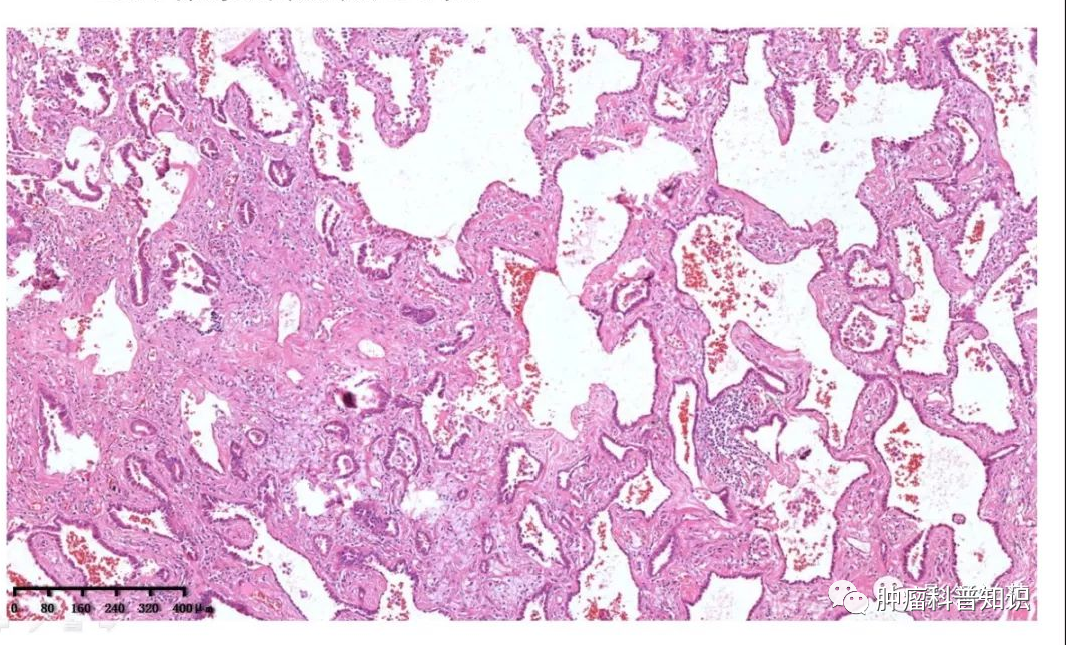

微浸润腺癌(MIA)

是原位癌的进一步发展,不超过5mm的浸润,如果没有得到及时的治疗,癌细胞就会继续发展,穿破基底层,发展成为微浸润腺癌,有转移和扩散的能力。

浸润腺癌(IAC)

是微浸润性腺癌的进一步发展,当微浸润性腺癌没有得到及时的治疗,癌细胞就会继续发展,就变成了浸润癌。浸润癌分为早期和晚期,早期浸润癌没有出现远处扩散和转移,可以通过手术进行根除。晚期浸润腺癌出现了癌细胞局部扩散,只依靠手术治疗回天乏术,还需要同时进行放化疗。